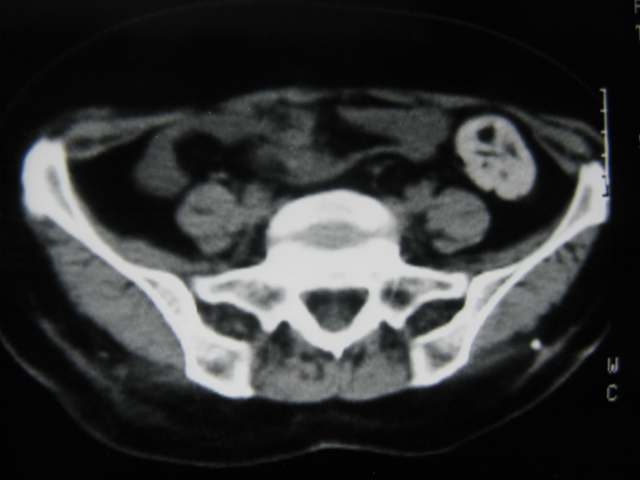

患者,女,64岁,2002年诊断为宫颈癌,当时只做过放,化疗。现在诊断:(1)宫颈癌。(2)直肠癌。请同道们讨论,探讨。另外肠壁为啥密度这么高,ct值约112hu。患者没有做过增强和造影。

高密度的不是肠管影,是肠管内的粪便影

患者直肠病变,排便不畅,粪便硬结造成,更高密度如钡灌肠者都可出现

硬结粪便能有如此高密度影?

患者是否长期服用抗癌药物?应与服用药物有关!

是否与放、化疗有关?

我也碰到过几例,最离奇的一例是全结肠呈造影样高密度,患者直肠癌(首次发现),以往没有吃药,只有约半年时间长的胃纳差,排便不畅(据患者说每次大便只能拉出少许黄水)

不一定有意义,可清洁灌肠后复查